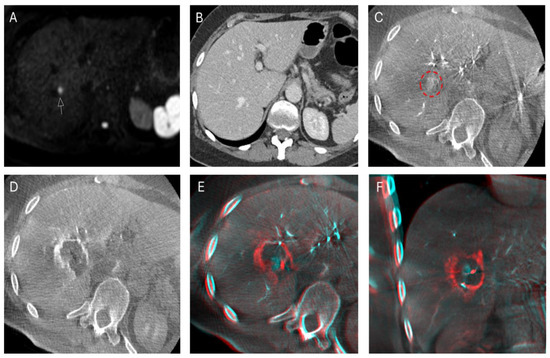

2.3. Imaging Protocol

2.4. Ablation

2.5. Study Objectives

2.5.1. Technical Success

3.2. Technical Success

3.3. Local Tumor Progression